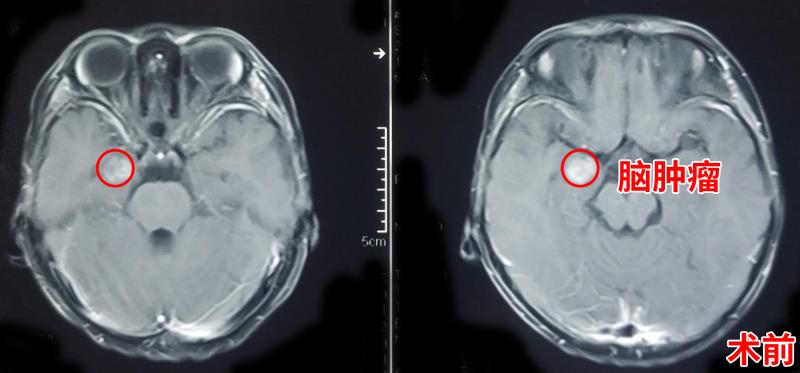

杰杰很快住进了三博脑科医院神经外科三病区,孙玉明仔细询问了孩子的病情。从影像资料来看,杰杰颅内右侧颞叶内侧有一团片状异常的信号影,大小约2.5厘米大小,初步判断孩子的病变可能是脑肿瘤,而杰杰的这些奇怪的症状就是这个肿瘤引起的癫痫发作。

经过术前的病例讨论,完善术前相关检查,杰杰被推进手术室,孙玉明等神外三病区团队为杰杰实施了开颅肿瘤切除术,术中完好保护了重要的血管和神经以及相邻脑组织,肿瘤被全切除。术后,杰杰恢复良好,在病房和妈妈有说有笑,互动良好,让家人揪心的癫痫也没有再次发作。